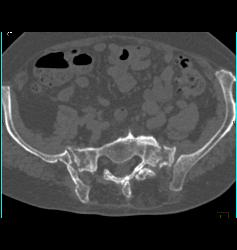

Stress Fracture in Sacrum